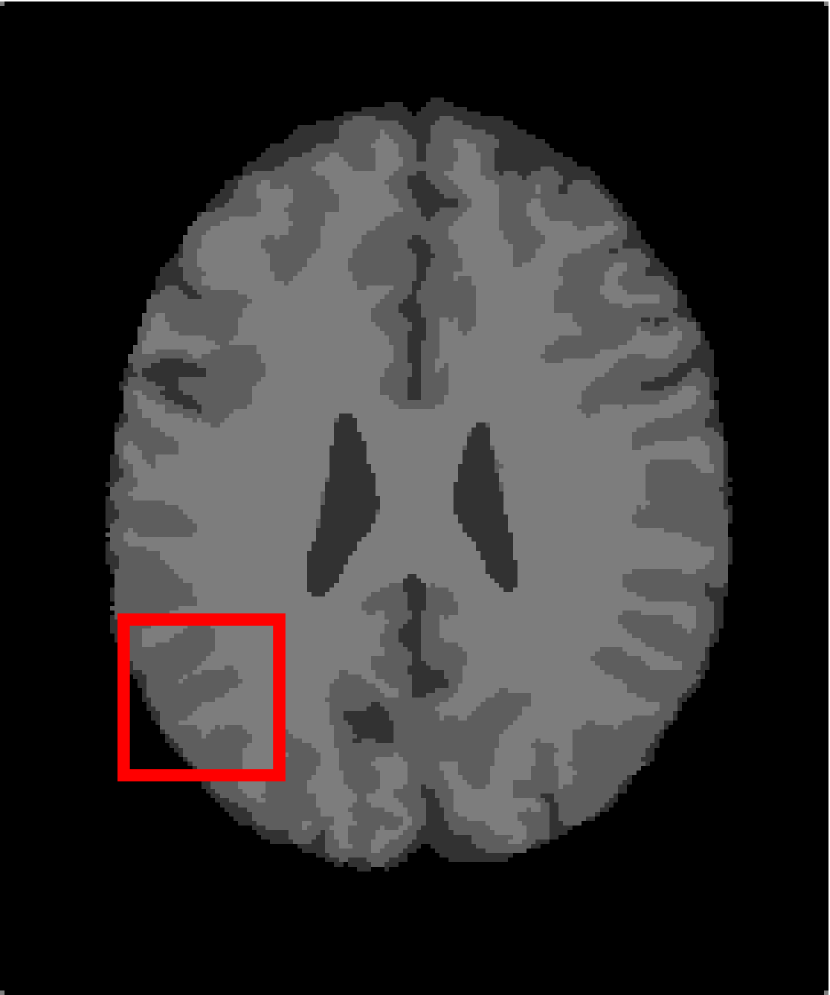

In the second experiments, we segment two medical images coming from a simulated brain database (BrianWeb): http://www.bic.mni.mcgill.ca/brainweb/. The two images are generated by T1 modality with slice thickness of 1mm resolution, 9% noise and 20% intensity non-uniformity. Here, the two images are represented two slices in the axial plane with the sequence of 100 and 110. Moreover, there are golden standard segmentations in the dataset. We set the numbers of clusters to 4. The visual comparisons are illustrated in Figs. 6 and 7.

Figure 6: Segmentation results for the first medical image. From (a) to (l): ground truth, noisy image and results of FCM_S1, FCM_S2, FGFCM, FLICM, KWFLICM, ARKFCM, FRFCM, WFCM, DSFCM_N, and LRFCM.

By focusing on the marked red square in Figs. 6 and 7, we easily find that FCM_S1, FCM_S2, FGFCM and ARKFCM are sensitive to noise. FLICM and KWFLICM are vulnerable to severe intensity inhomogeneity. FRFCM brings overly smooth results due to the use of gray level histograms. WFCM and DSFCM_N cause several contours to change. However, LRFCM acquires clear contours and suppresses noise adequately. Moreover, we find that the segmentation result of LRFCM is closer to ground truth.